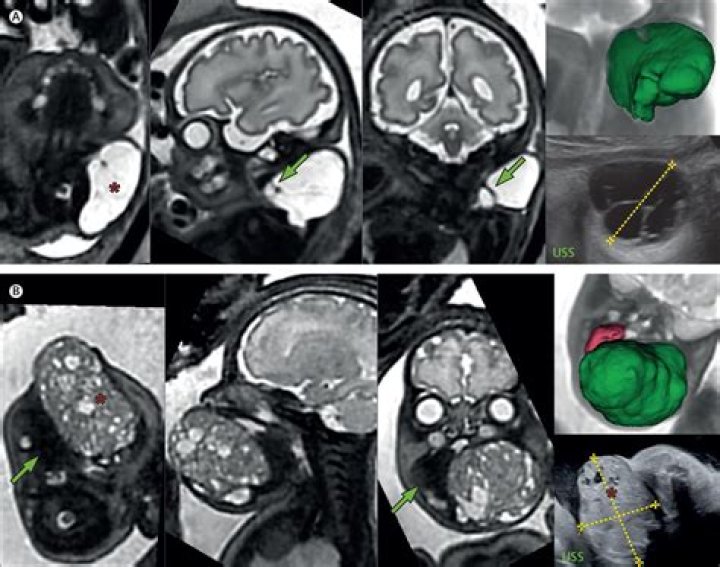

Can a child be born pregnant?

A baby born in Hong Kong was pregnant with her own siblings at the time of her birth, according to a new report of the infant's case. The baby's condition, known as fetus-in-fetu, is incredibly rare, occurring in only about 1 in every 500,000 births.